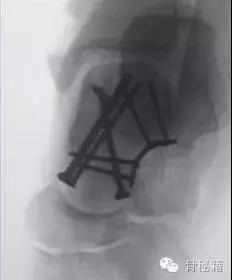

对于颈部的骨折,如果一侧钢板的位置不佳,则容易造成另外一侧的骨折裂开所以最好的固定是一侧用钢板固定,另外一侧可采用螺钉进行加压,避免另外一侧开口

要点!!1、骨折严重合并脱位的一定要早期临时外架牵引复位和维持一定要早期临时外架牵引复位和维持一定要早期临时外架牵引复位和维持重要的说三遍2、尽量保护血运,用单侧入路3、尽量避免关节面内置物4、注意皮肤软组织情况